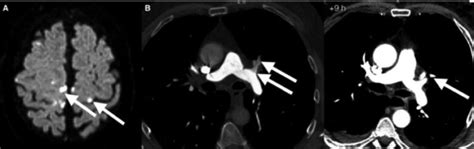

Knowing the symptoms of decompression sickness is super important, guys, especially if you or someone you know is involved in diving or high-altitude activities. These symptoms can pop up anywhere from a few minutes to even 24 hours after a pressure change, so it’s not always immediate. The most common and often the first sign is joint pain , often called ‘the bends.’ This pain can be pretty intense and usually affects the shoulders, elbows, and knees. It’s like a deep, throbbing ache that makes moving difficult. Beyond joint pain, you might experience other issues. Skin manifestations can include itching, a mottled rash (known as skin mottling), or even small red bumps. Some people report a feeling of pins and needles, numbness, or tingling, which is a sign that bubbles might be affecting nerves. Neurological symptoms are some of the most concerning and can range from dizziness, vertigo, and confusion to more severe issues like blurred vision, difficulty speaking, weakness or paralysis in limbs, and even loss of consciousness. Respiratory symptoms can also occur, such as shortness of breath or chest pain, which can indicate bubbles affecting the lungs. If you experience any of these symptoms after a dive or a rapid ascent, it’s absolutely crucial to seek medical attention immediately. Don’t try to tough it out. Divers typically use the phrase ‘when in doubt, get it out,’ meaning if you suspect DCS, get to a recompression chamber or medical professional. Early recognition and treatment significantly improve outcomes. So, keep this list handy and stay vigilant. Your health and safety are paramount, and recognizing these signs could be a lifesaver.